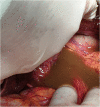

Introduction: The gastric volvulus is a rare condition in which the stomach, or part of it, rotates on its axis, for over 180°, constituting a surgical emergency. Even more rare is gastro-gastric intussusception. A delay in their diagnosis and treatment can have fatal consequences PRESENTATION OF CASE: An 82-year-old woman was admitted to the Surgery Unit with a two-day history of abdominal pain associated at first with coffee vomiting and, subsequently, with unproductive retching and oligoanuria. Physical examination showed severe dehydration, fever, at the abdominal level, palpation caused a marked tenderness of all quadrants, with signs of peritonism. Laboratory test showed showed neutrophilic hyperleukocytosis and high C reactive protein level. Abdominal computed tomography revealed an acute intrathoracic gastric volvulus and a gastrogastric intussuception. The patient was submitted to exploratory laparotomy, subtotal gastrectomy with Roux en Y anastomosis and simple plastic of the esophageal hiatus. At the end of the surgery, however, the patient died of your septic shock.

Discussion: The traditional treatment for a patient with acute gastric volvulus is an immediate surgical intervention to derotate the stomach and prevent vascular insufficiency. In the presence of necrosis or gastric perforation, resection should be performed. The few cases of gastrogastric intussusception described in the literature have been treated with sub-total gastrectomy and gastro-jejunal anastomosis. Any delay in diagnosis and treatment can prove fatal.